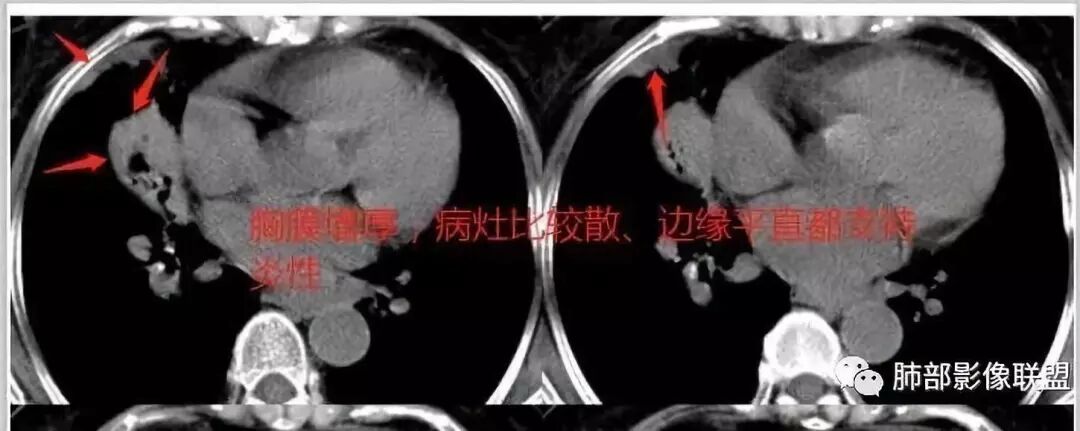

丁啸:

有没有和典型的粘液腺癌不符合的地方

我觉得这个长轴和支气管平行,不是和胸膜平行。不是起源于胸膜下,病灶比较密实,内部粘液密度不多,这是不符合地方。当然也有很恶性的特点,

这些层面的支气管我觉得像结核的狭窄后扩张,

纵隔窗,没有看到太多细支气管里粘液的密度。

中叶的体积缩小,也不是粘液腺癌能完全解释,